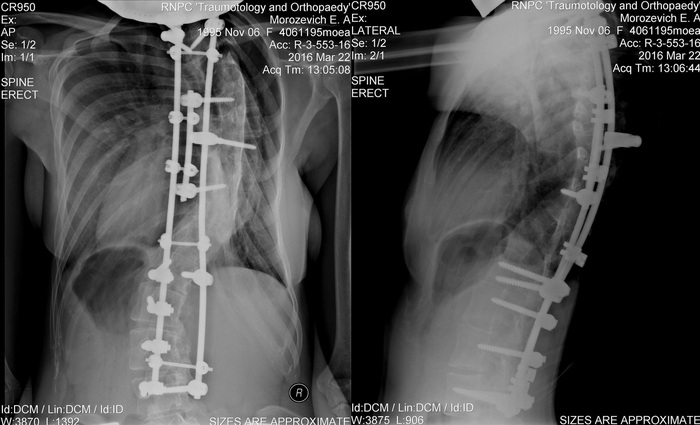

Принцип операции был похожий. Ты находишься под общим наркозом, тебя и твой позвоночник растягивают и следят за показателями организма, на сколько максимально возможно выпрямить позвоночник. Далее его фиксируют титановыми штифтами и болтами. Операция длится 8 часов, посреди операции тебя еще и будят, просят пошевелить руками и ногами, но ты это конечно даже не запомнишь и не вспомнишь)

Операцией получилось исправить искривление до 75 градусов.

После операции мне стало легче дышать, пропала отдышка. А еще я стала выше своей мамы, т.к. рост увеличился на 10 сантиметров.

Мне стало настолько легче жить после операции! Я быстро набрала вес, около 10 кг. Я стала намного лучше выглядеть и чувствовать себя, стала увереннее, Я РАСЦВЕЛА :) Фото 2015 года:

Стало намного легче дышать, ходить, а самое главное пропали боли в спине и до сих пор, вот уже как 8 лет их нет. Чувствую себя здоровым человеком. Титановую конструкцию внутри себя не ощущаю.